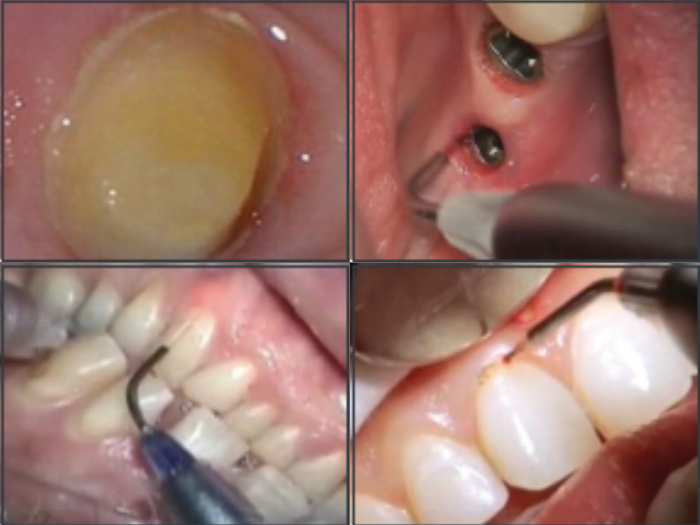

Soft Tissue before & after photos